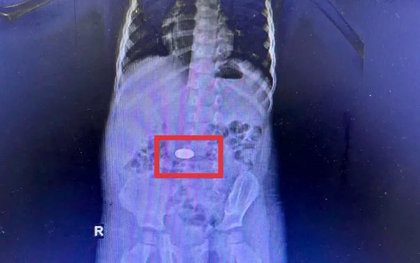

Cảnh báo liên tiếp trẻ nuốt đồng xu nhập viện

Chỉ trong tháng 11, Bệnh viện Đa khoa Khánh Hòa tiếp nhận 5 trường hợp trẻ nuốt đồng xu phải nội soi khẩn cấp.